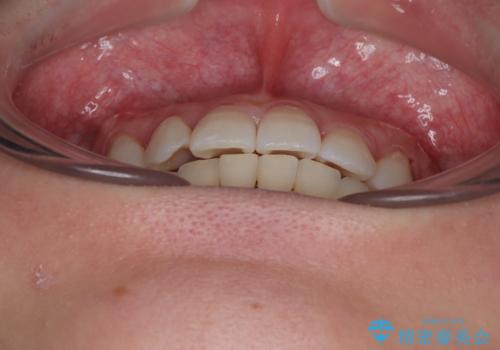

捻転の強い前歯 ワイヤー装置での非抜歯矯正

当初予定通り1年半ほどの治療期間で、非常に綺麗な歯列に仕上げることができました。

適合や携帯の悪いプラスチックのクラウンが装着されていたため、矯正治療後にオールセラミッククラウンによる補綴治療を行うこととしました。